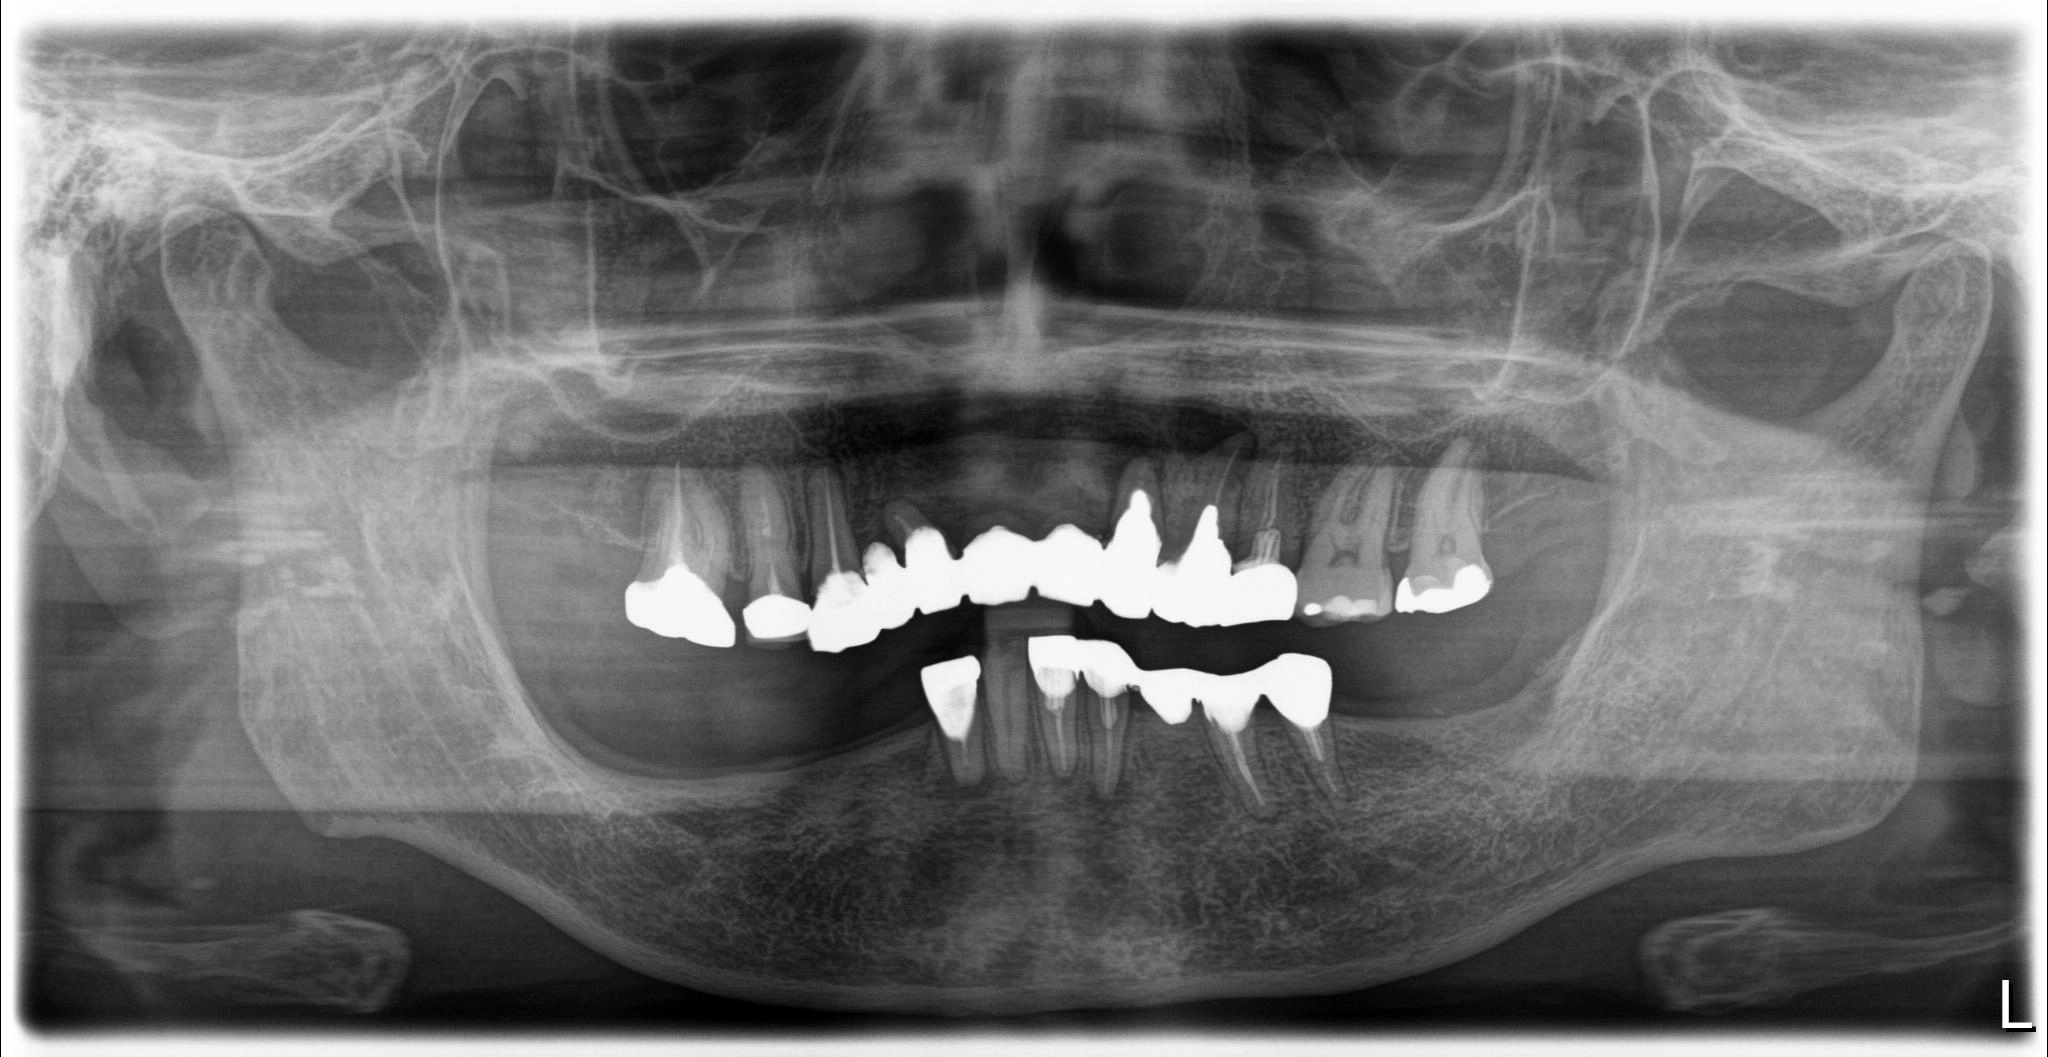

術前

内容 :上下顎オールオン4ザイゴマ2

費用 :5,899,850円

※モニター価格

期間 :半年

リスク:出血・腫れ・痺れ・痛み